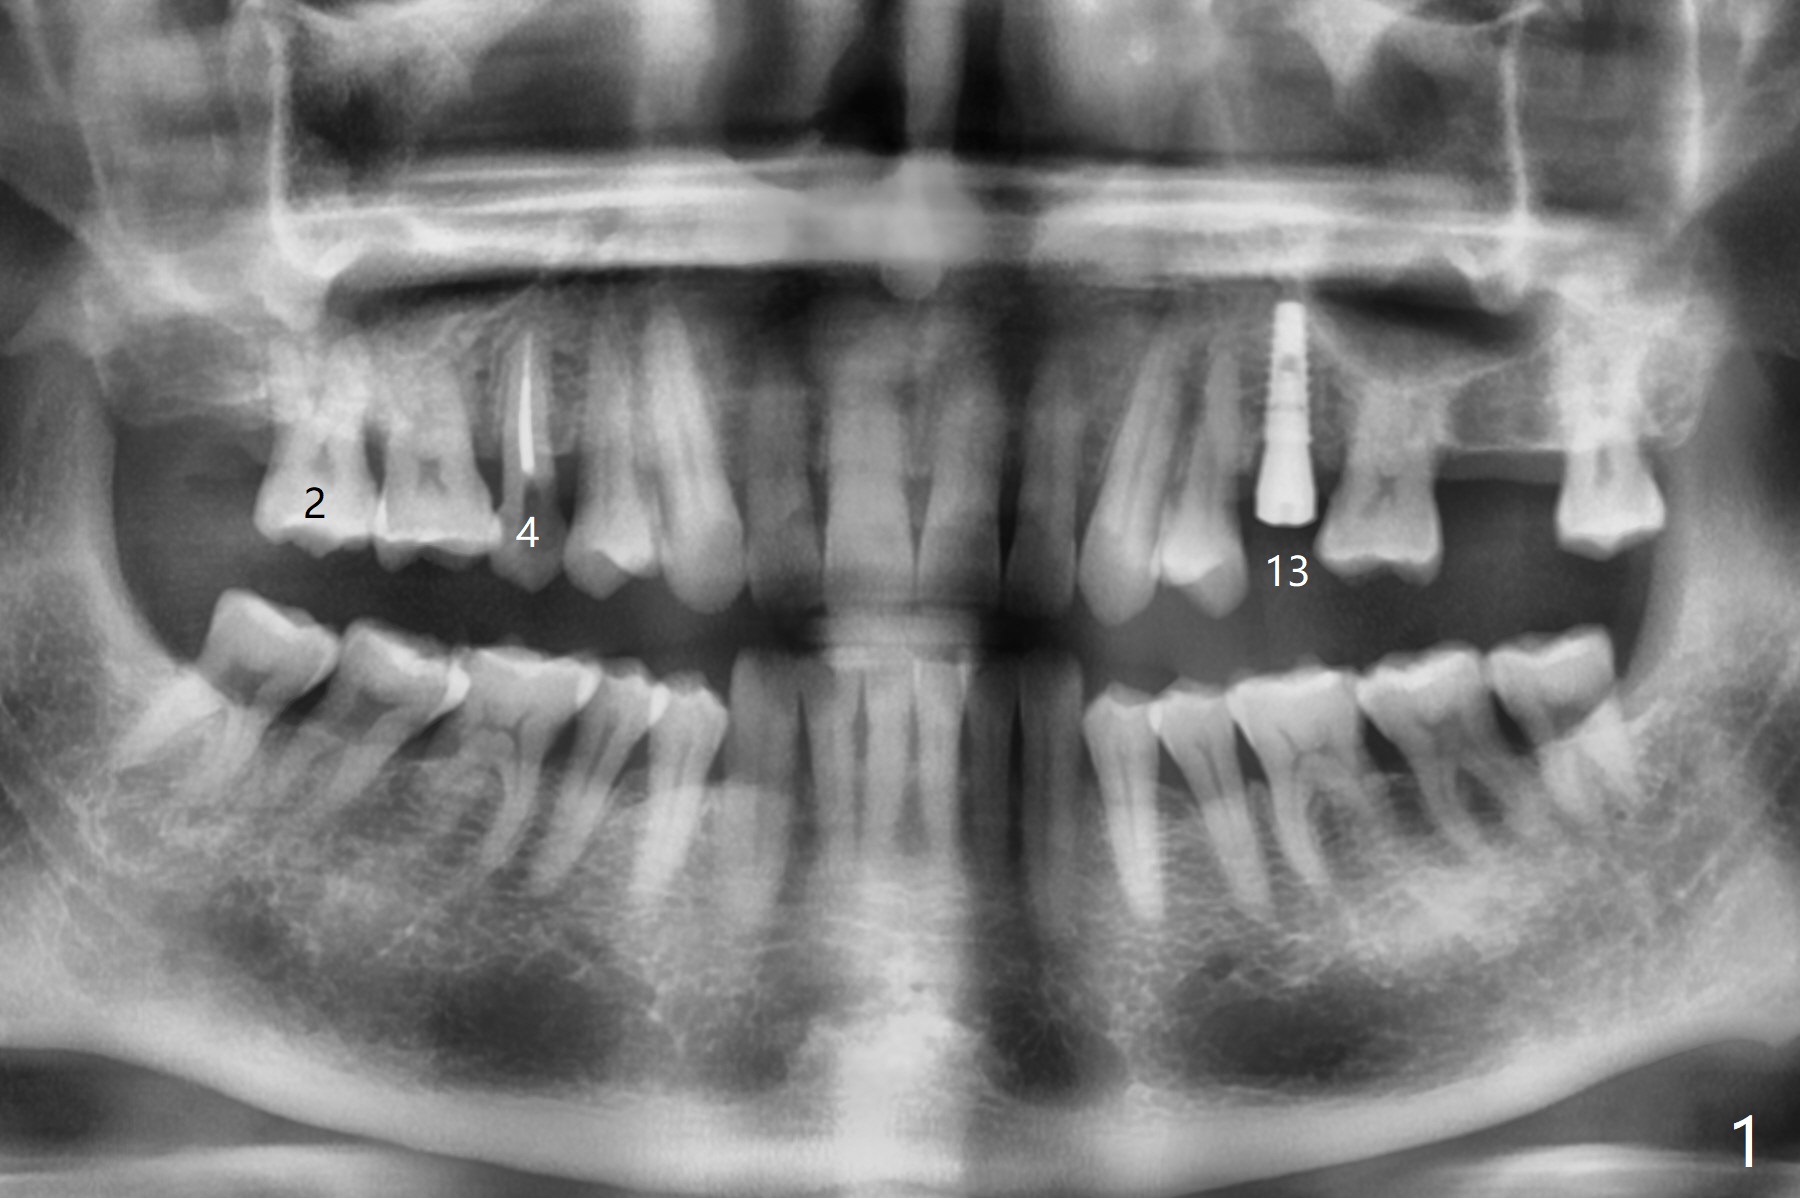

After implant placement at #13 six months post bone graft (Fig.1), reexami-nation shows that the tooth #2 cracks (Fig.2-4). The bony defect area is easier to identify with CT (between MB and P roots of #2) than without CT (M) for #13. There is no bone height reduction after extraction of #15 (Fig.5). Due to new coronal virus outbreak, the patient wants extraction first. The sinus floor perforates (*) apical to MB (Fig.6) and DB (Fig.7) roots. After debridement, sinus lift will be conducted using allograft hydrated with GEM21S liquid portion. The same mix will be used for socket preservation. With high concentration of growth factor, it is hoped that bone density in the sockets will increase quick and high enough for future implant, as compared to #13 of the same patient.

Dr. Lynch: Tomorrow sinus lift will be conducted through #2 extraction sockets. Is GEM21S liquid portion indicated? Thanks. On Mar 17, 2020, at 8:00 PM

Yes, there have been several peer reviewed publications using rhPDGF plus mineralized allograft in sinus lifts. Good results. Some surgeons use same mix as in sockets, while others use this mixture and add in a little bone xenografts particulate such as GEM Bone Graft for their sinus grafts.